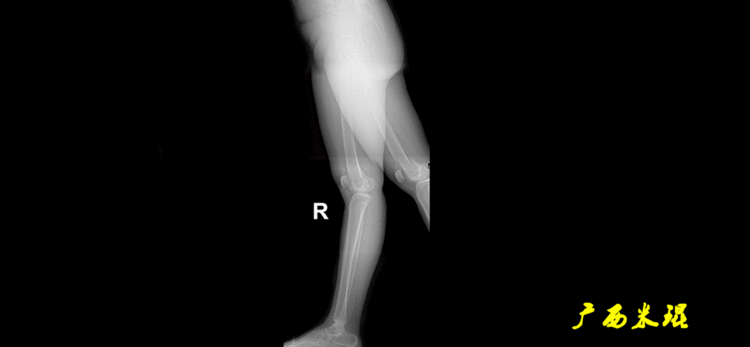

下肢力线及相关角度测量的前提是必须拍摄标准的站立位也就是负重位的下肢全长片。目前这样的照片都是放射科的技师在电脑上拼接出来的,大部分医院的DR都能够做到这一点。

患者直立于摄影架上,后背贴近摄影架,双手自然下垂,膝关节尽量伸直,足部与双肩同宽,要求投照时双髌骨朝正前方,通常患者双足尖应平行向前即可。

提醒一下大家,拍摄过程中应避免下肢的外旋和内旋。如果有一侧肢体短缩时,投照应当用脚垫垫高短缩肢体,使骨盆保持水平,这样下肢短缩测量才精确。如果有肢体旋转畸形时,还是以髌骨朝前为标准,虽然此时双足可能不能保持平行。

无论如何,拍摄出来的下肢全长片必须包含髋关节中心、膝关节中心及踝关节中心,否则对临床是无用的。有了一张下肢的全长照片,我们需要确定下肢关节的中心点,通过中心点画出下肢的各种轴线,然后利用轴线与关节线的相交得出各种所需要的角度。